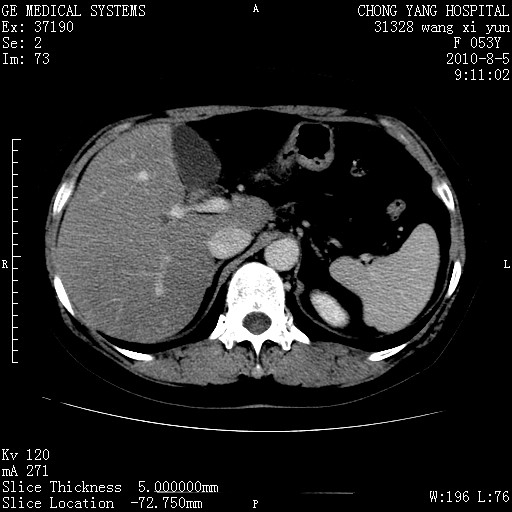

胆管细胞ca?

1)考虑肝左叶胆管细胞癌。2)脂肪肝。

支持胆管细胞ca。